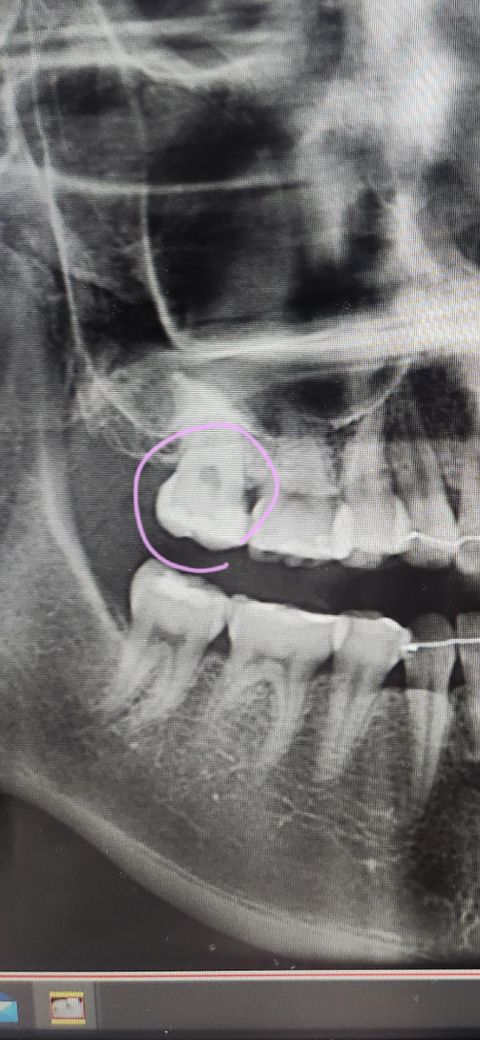

위 사진은 A치과이고 표시한 부분에 인레이 또는 신경치료를 권했습니다.

• 1번 째 사진